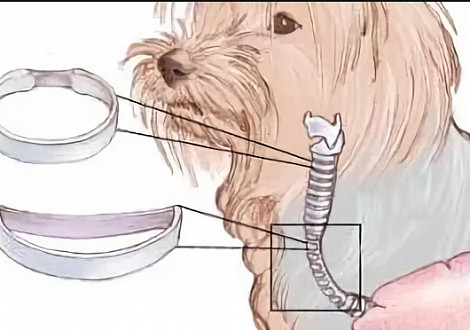

Для понятия процессов, возникающих при данном заболевании, рассмотрим анатомическое строение трахеи.

Trachea – трубчатый орган, соединяющий верхние и нижние дыхательные пути. Он является проводящей магистралью между гортанью и бронхами. Подразделяется на шейную и грудную части, зона наибольшей физической нагрузки находится в области перехода шейной части в грудную полость. Каркасом трахеи являются хрящевые полукольца, соединенные между собой соединительной тканью в виде связок и имеющие форму лежащей буквы «С». Верхние края полуколец соединены так называемой трахеальной мембраной, состоящей из мышцы; изнутри орган покрыт слизистой оболочкой. Нормальная трахея в поперечном сечении имеет круглую форму, которая на всем цикле дыхания остается неизмененной. Вышеприведенное строение трахеи придает ей значительную подвижность и адаптацию к различным видам нагрузок, характерных для нижнего отдела шеи и перехода в грудную полость.

У собак маленьких и миниатюрных пород имеется предрасположенность к деформации просвета трахеи в каудальной шейной части и краниальной грудной. Конкретная причина такого явления на сегодняшний день точно не определена, существует несколько вариантов начиная от дегидратации хряща полукольца и заканчивая концентрацией содержания гликозаминогликанов в его матриксе. На сегодняшний день точно известно одно: существует склонность к коллапсу трахеи у собак таких пород, как йоркширский терьер, карликовый шпиц, чихуахуа, той-терьер, миниатюрный пудель. Данным заболеванием подвержены собаки любого возраста и пола. Клиническая картина характеризуется такими симптомами, как кашель и диспноэ различной степени, которые зависят от степени пролапса дорсальной мягкотканой стенки и жесткости трахеальных колец.